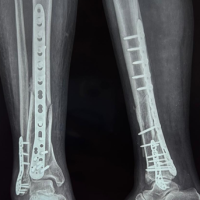

Out of 138 fractures, 107 (77.5%) achieved union, whereas 31 (22.5%) resulted in non-union. Univariate analysis revealed that the Gustilo-Anderson grade, treatment modality, time lag to treatment, and presence of diabetes mellitus were significantly associated with non-union. The non-union rate increased progressively with higher Gustilo-Anderson Grades – 3.3% in Grade I, 20% in Grade II, 54.8% in Grade IIIA, and 66.7% in Grade IIIB (P < 0.001). The type of treatment also had a significant impact, with nailing showing the lowest non-union rate (8.5%), while Ilizarov (66.7%) and LRS (41.7%) had higher rates (P < 0.001) (Graph 6 ).

Graph 6: Showing types of treatment.

The mean time lag was 5.2 days in the non-union group and 4.2 days in the union group (P = 0.02). The presence of diabetes mellitus was also significantly associated with non-union (P = 0.001). On multivariate logistic regression analysis, only the Gustilo-Anderson grade emerged as an independent determinant of non-union with an OR of 5.604 (P = 0.001). Similarly, the same parameter was found to be the only independent determinant for other complications (OR 1.779, P = 0.017). Functional outcomes assessed using the Barthel index, soft-tissue healing time, and duration of hospital stay, demonstrated a significant correlation with the severity of soft-tissue injury. The Barthel index was markedly lower among patients with Grade IIIA and IIIB fractures (mean 80.6–80.8) compared to those with Grade I fractures (90.9, P = 0.00). The mean soft-tissue healing time was 35.0 days in Grade IIIA cases and 15.2 days in Grade I fractures (P = 0.00). Similarly, the mean duration of hospital stay was significantly longer in Grade IIIA patients (20.0 days) compared to Grade I (8.8 days, P = 0.00). These findings indicate that higher Gustilo-Anderson grades are associated with poorer functional outcomes and prolonged recovery (Table 1-4).